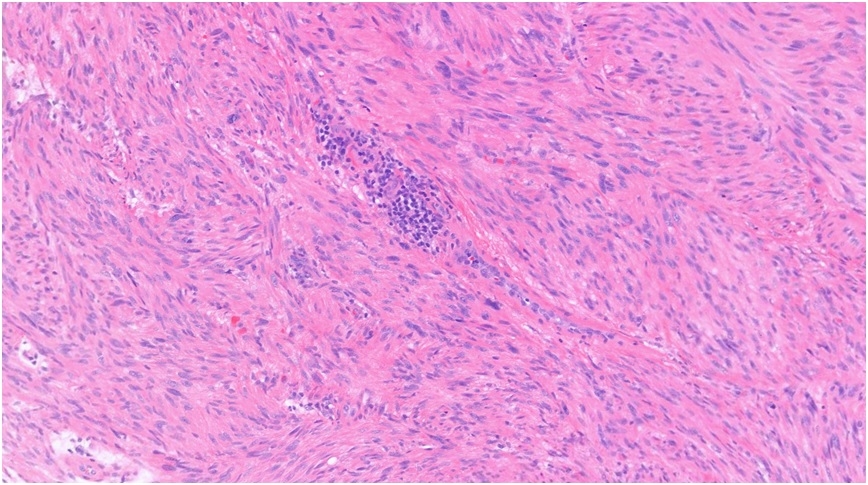

44F, Right shin Excision to exclude DFSP Dermatofibroma (13.10.22) Sudden recurrence of 2x tender lumps on this site; pink, tender 15 mm x 5 mm